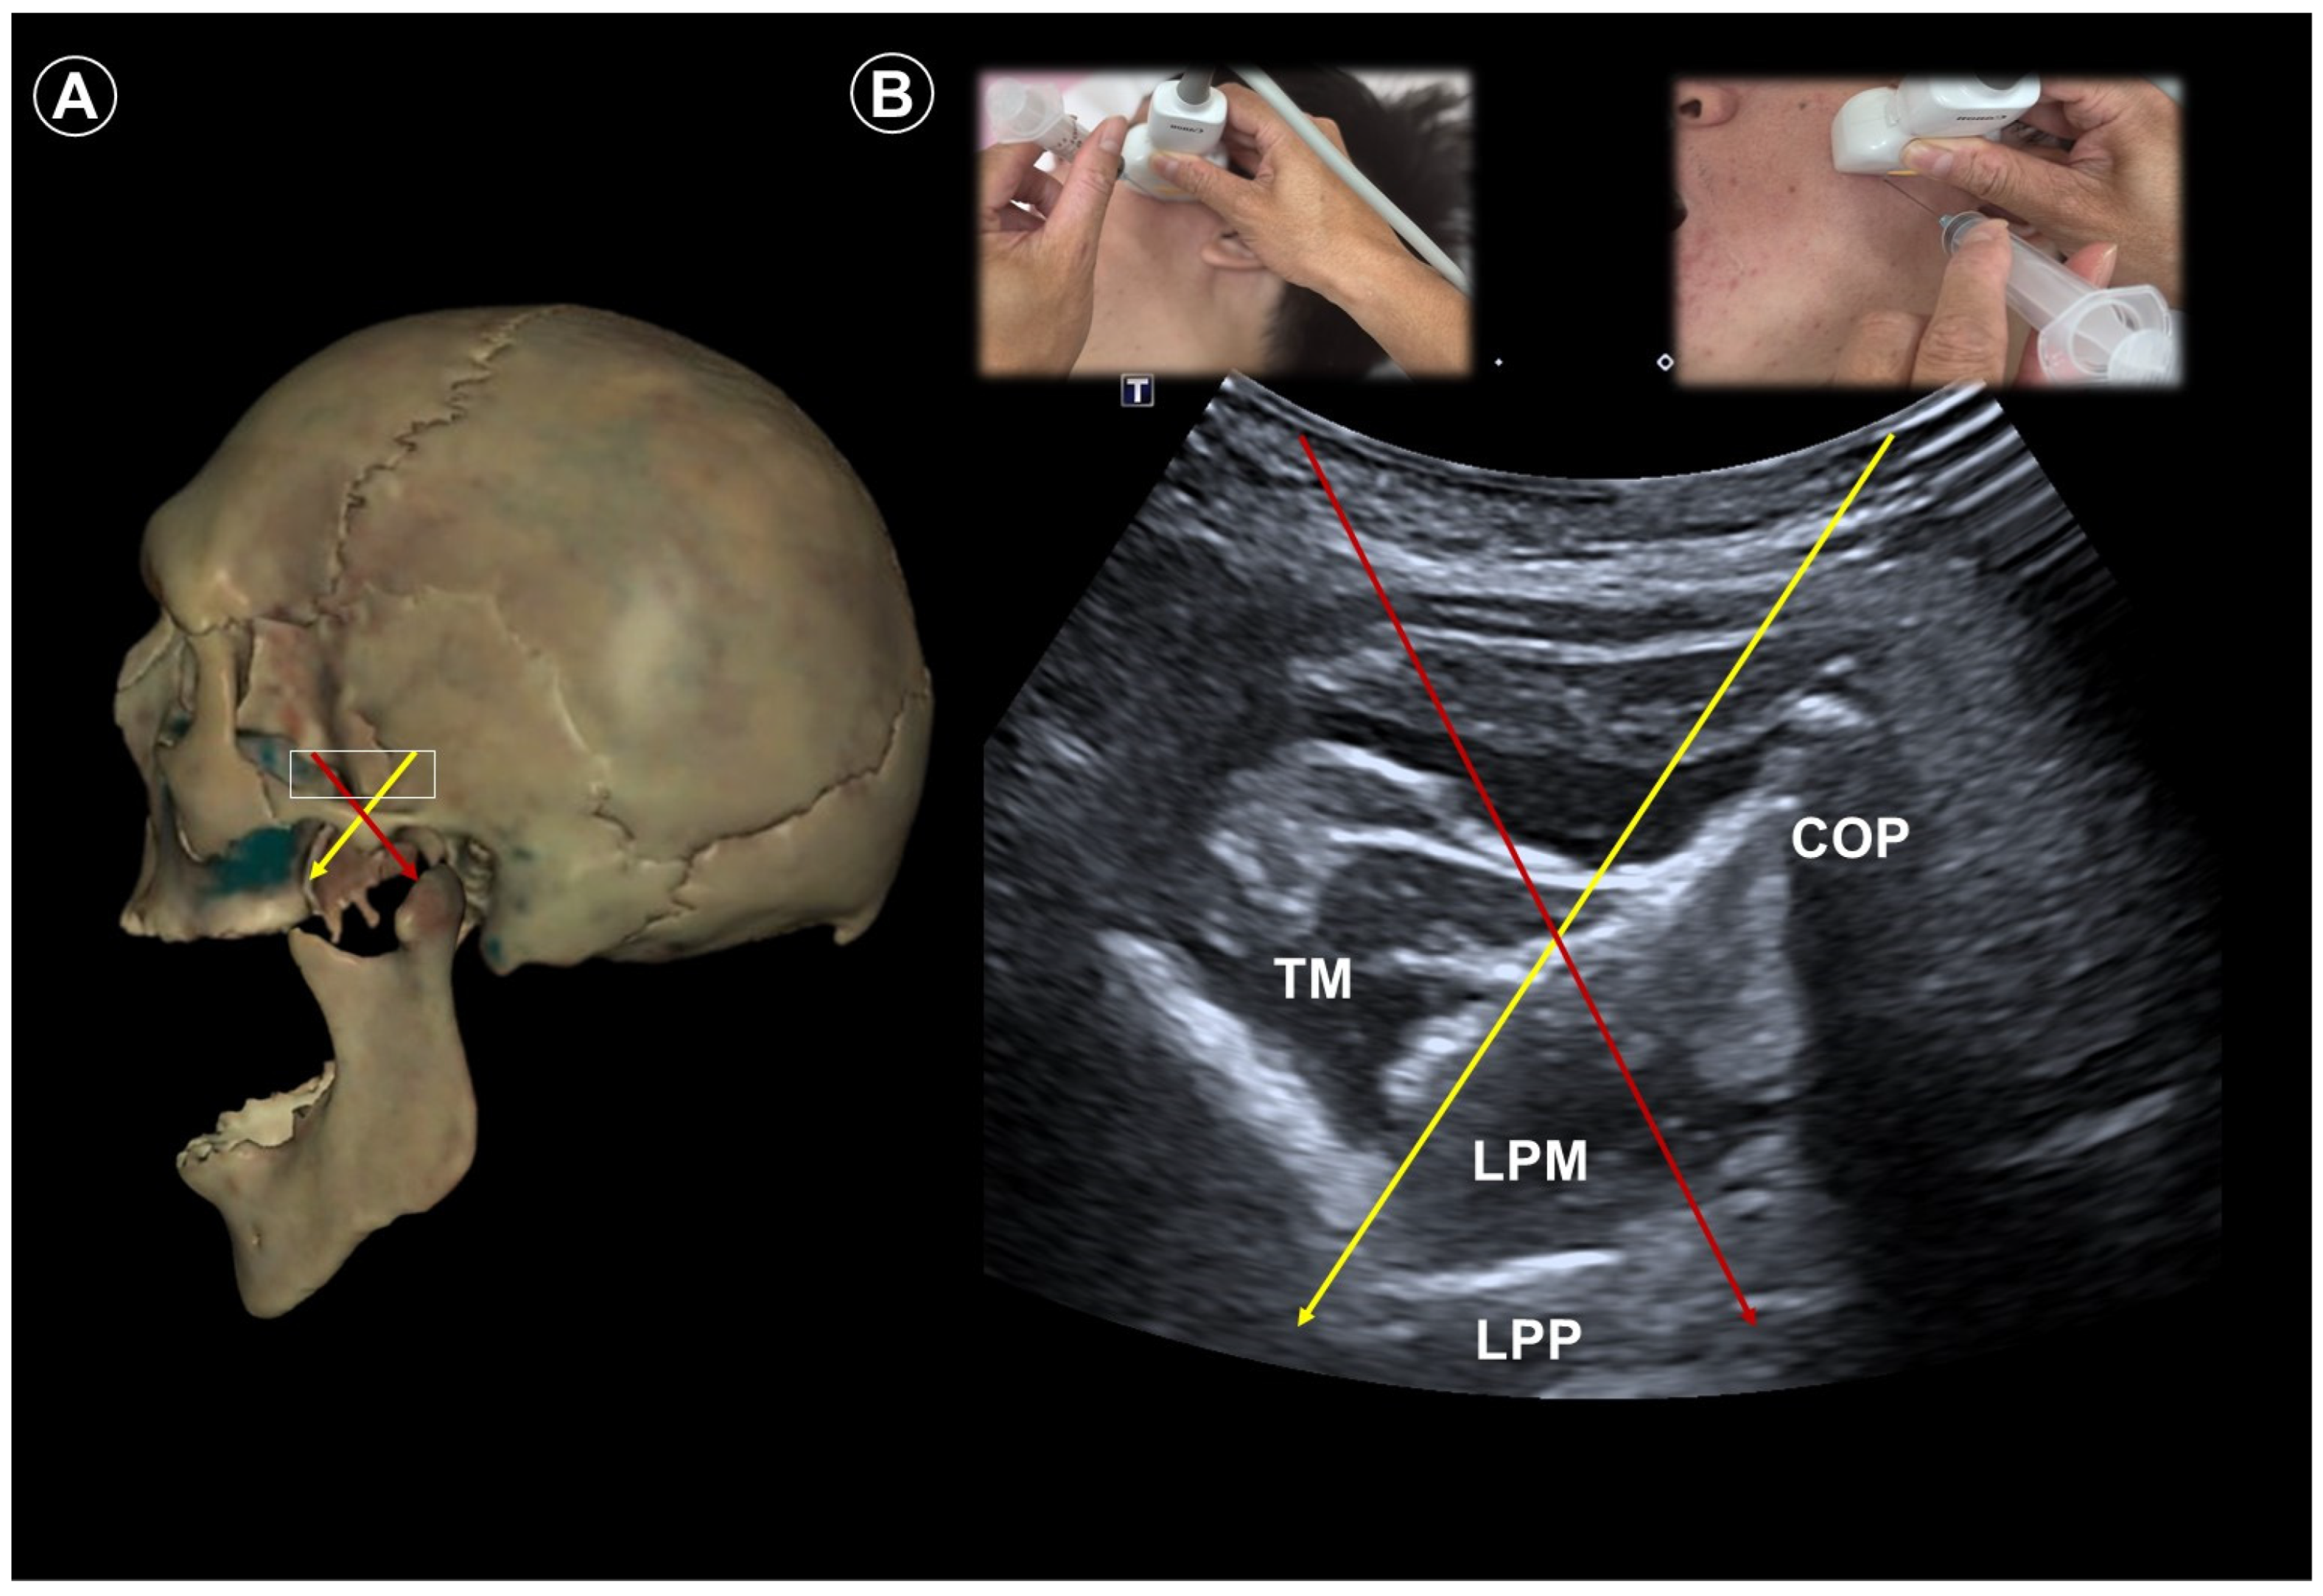

- Allam, A.E.; Khalil, A.A.F.; Eltawab, B.A.; Wu, W.T.; Chang, K.V. Ultrasound-Guided Intervention for Treatment of Trigeminal Neuralgia: An Updated Review of Anatomy and Techniques. Pain Res. Manag. 2018, 2018, 5480728. [Google Scholar] [CrossRef]

| Trigeminal neuralgia | Paroxysmal facial pain in one or more divisions of the trigeminal nerve | Neurovascular compression at root entry zone | Head neutral | Linear probe, in-plane

| Lateral, with affected side up | Curvilinear probe, out-of-plane